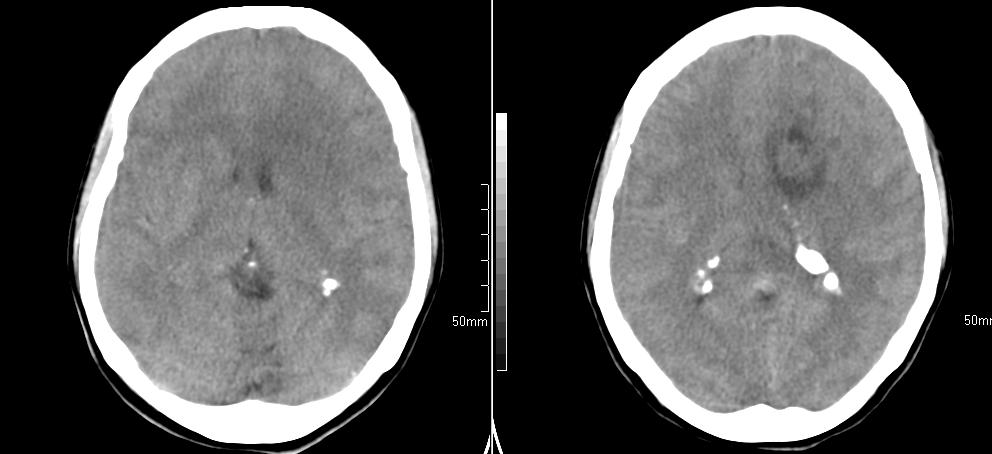

标题: CT23966:女,34岁,近一月头痛、意识障碍 [打印本页]

标题: CT23966:女,34岁,近一月头痛、意识障碍

左侧额叶见不规则软组织影,部分囊变,病变略呈等密度,占位效应明显,考虑血母可能。脑膜瘤不除外

左额叶囊实性肿块,实性部分呈等密度,密度不均,考虑胶质瘤可能性大,脑膜瘤及室管膜瘤不除外,建议mri增强扫描。

左额叶低分化星形细胞瘤或胶质母可能性大。建议增强。

左额叶较大等低混杂密度影,占位效应明显,首先考虑:左额叶胶质瘤。